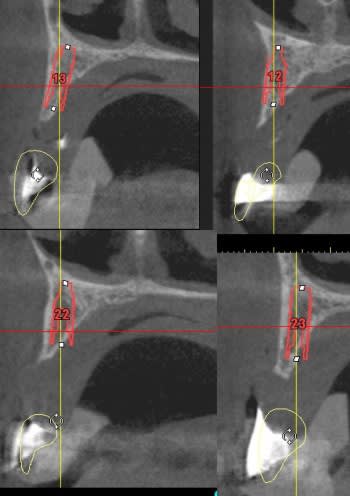

vis de cicatrisation sur une expansion réalisée en mars 09 à Sallanches implants en 13/14/15/18 pour une barre et PT.

Interessante car fracture de l'os vestibulaire y compris de la bosse canine, vitalos mais pas de vis d'ostéosynthese, et comme je sais que le doute est toujours present, ouverture large, avec décollement plus que necessaire pour controle.

sur l'implant en 14 une feuille d'os , en 13 un petit creux en mesio vestibulaire et 15 nickel.

18/17 et 28/ 27 en flapless (4 SL )

le gros point noir c'est 15, je ne suis pas sur que la solution soit de poser un implant de suite.

13 et 12 ça va le faire il te restera 22 23 et 24.